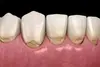

La mylolyse dentaire ou lésion cervicale d'usure

Elle se caractérise par une cavité située dans la partie cervicale de la dent, c’est-à-dire au niveau de la jonction entre la couronne et la racine. Cette lésion est brillante, dure au sondage et peut prendre une légère coloration brune.

Ce défaut de la dent n’est pas lié à une carie.